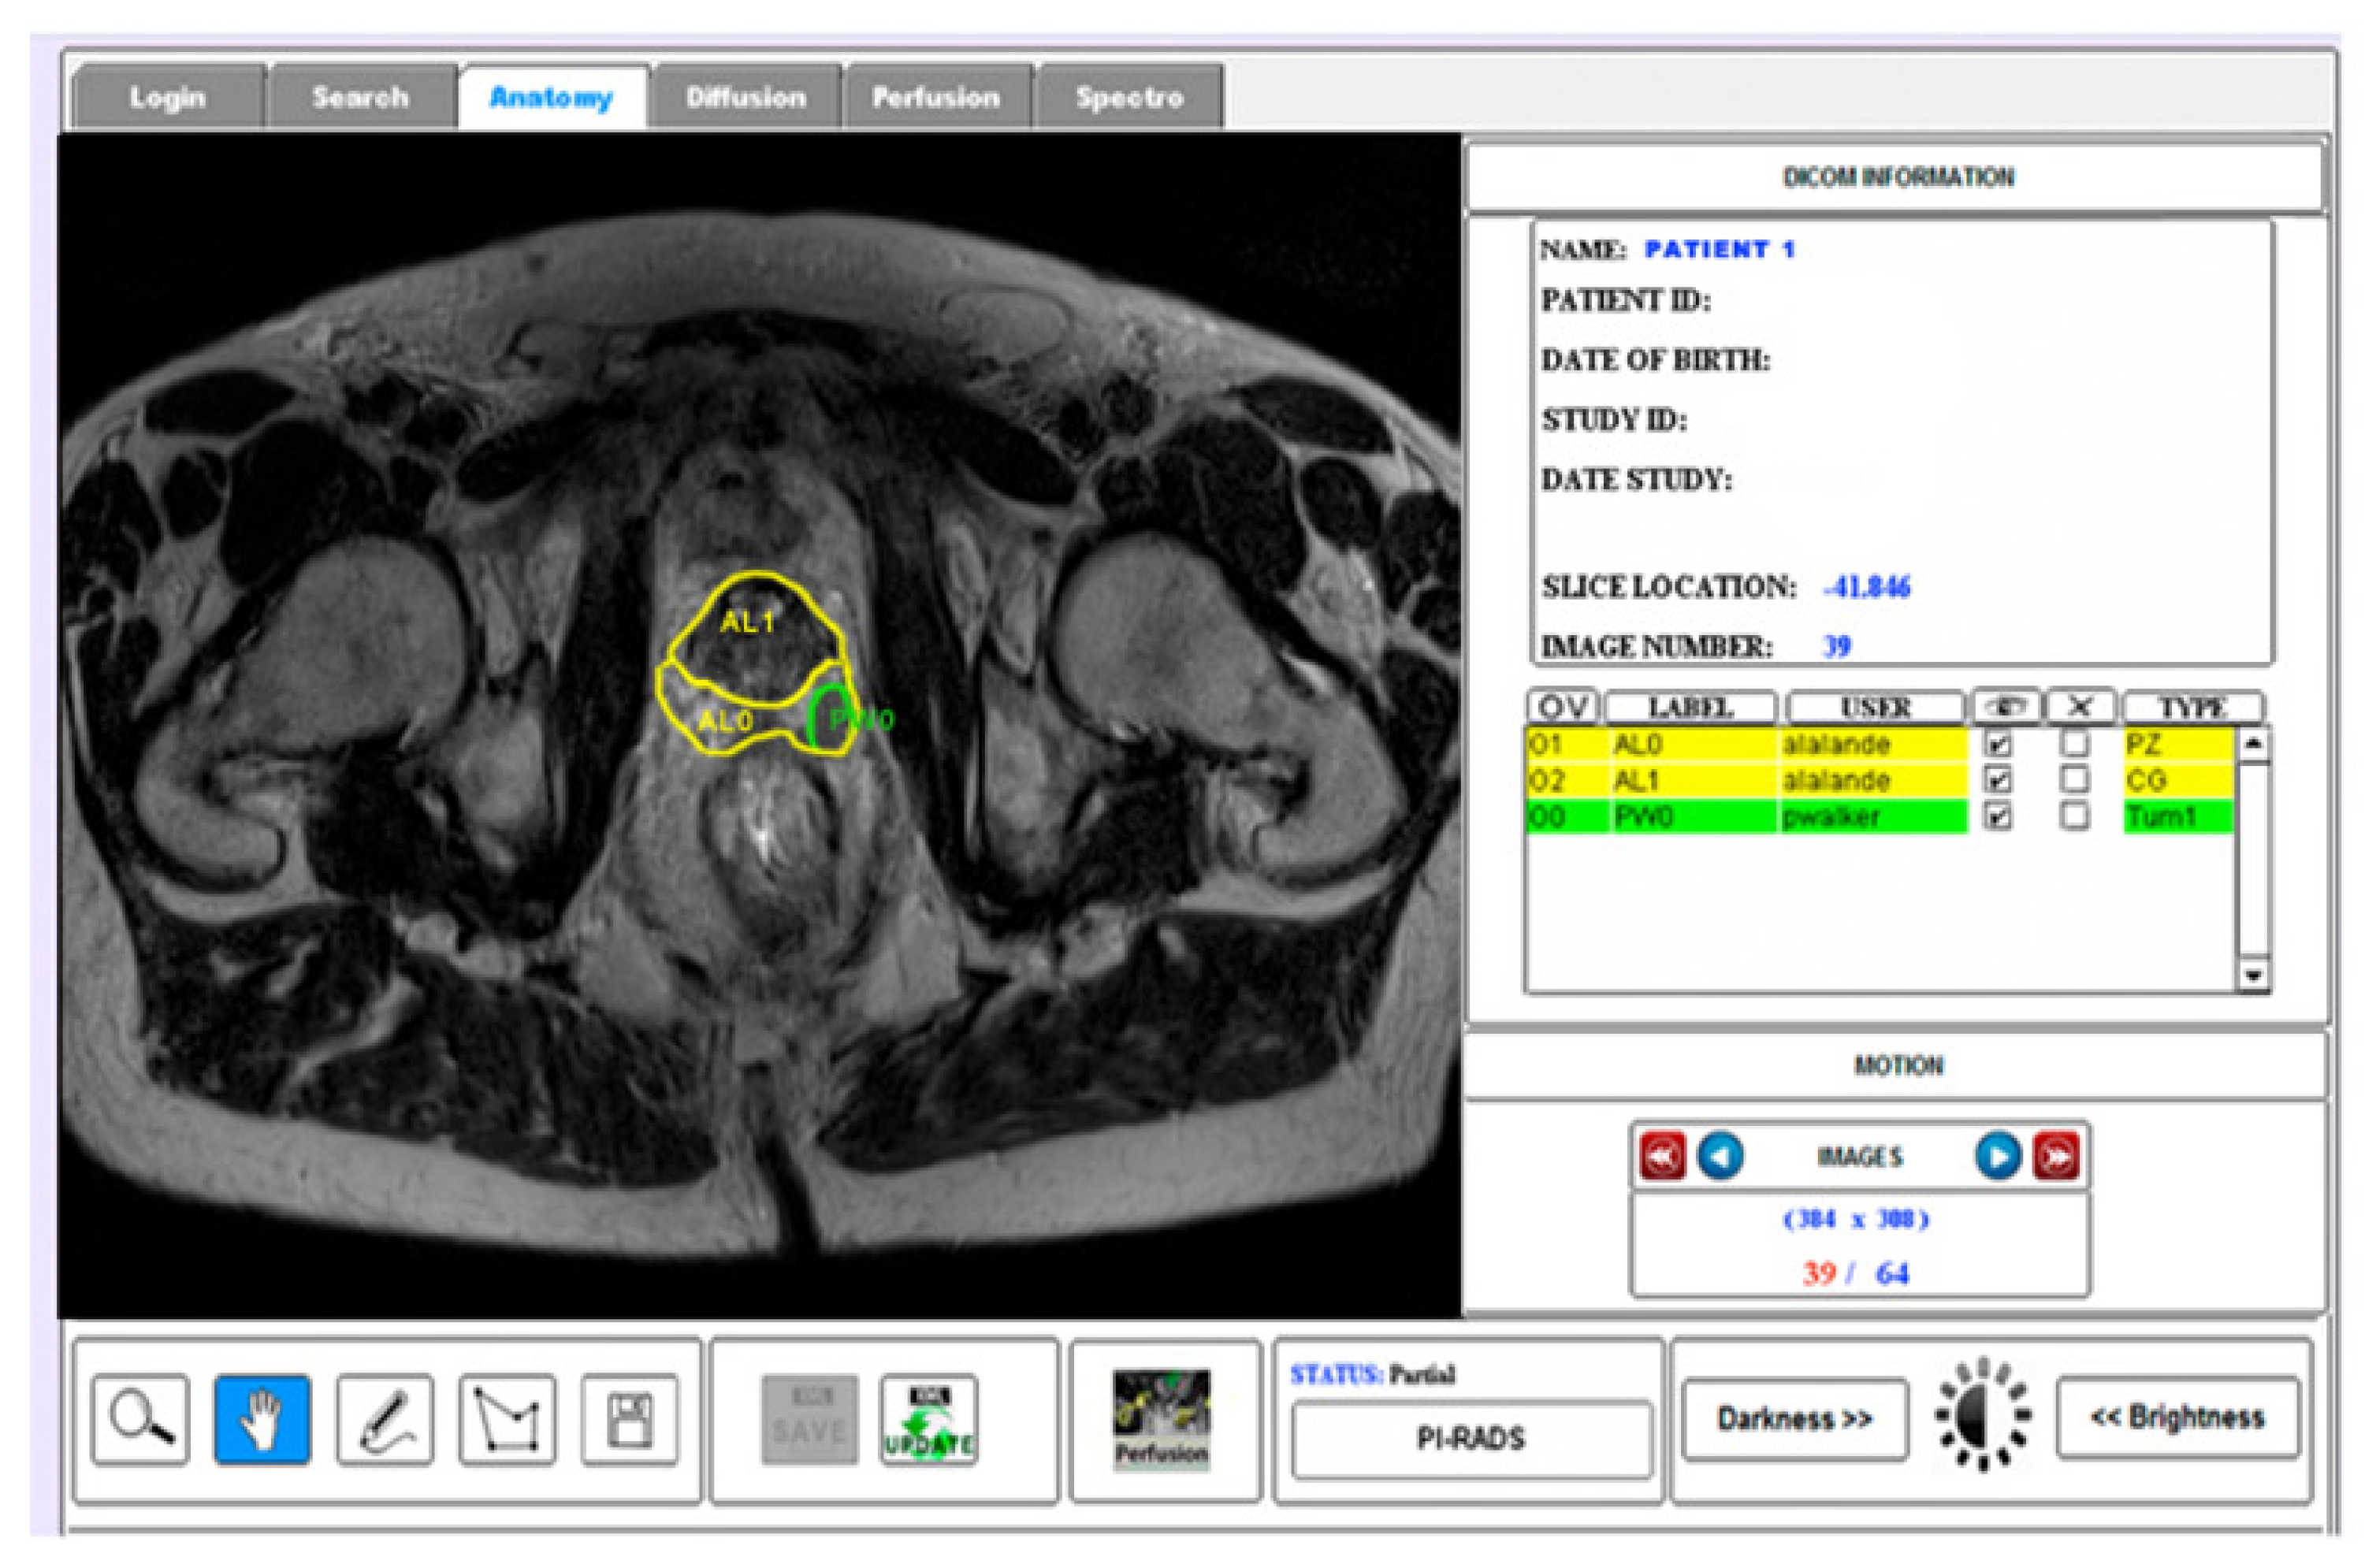

- Mata, C.; Walker, P.; Oliver, A.; Brunotte, F.; Martí, J.; Lalande, A. Prostateanalyzer: Web-based medical application for the management of prostate cancer using multiparametric mr images. Inf. Health Soc. Care 2015, 87, 1–21. [Google Scholar] [CrossRef]

- Romagosa, J.; Benitez, R.; Mata, C. ProstateAnnotation: Web-Based Application for Medical Imaging. IEEE EMBS International Conference on Biomedical and Health Informatics (BHI). 2021. Available online: https://www.bhi-bsn-2021.org/?page_id=2336 (accessed on 29 July 2021).